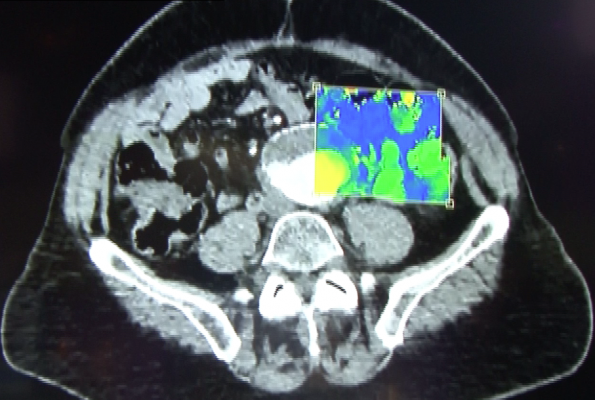

IQon Spectral CT image courtesy of Philips Healthcare

Confident diagnoses often depend on insight-yielding images. With Philips IQon Spectral CT, which the company calls the world's first spectral detector-based CT (computed tomography) scanner, one scan delivers the data needed to make a confident diagnosis. The IQon Spectral CT captures spectral information 100 percent of the time, empowering physicians to improve clinical confidence.